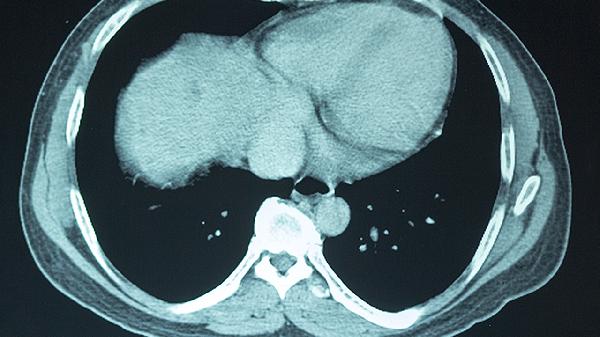

严重创伤或脑卒中导致的前额叶大面积梗死,通常伴随不可逆的神经元死亡。这类患者可能出现持续的性格改变和决策障碍,但通过代偿性训练仍能获得部分生活能力。强制性运动疗法可强化健侧半球支配功能,药物如多巴胺受体激动剂能改善动机缺乏。对于肿瘤压迫病例,手术解除占位效应后配合语言逻辑训练,约半数患者社会功能可达到代偿水平。